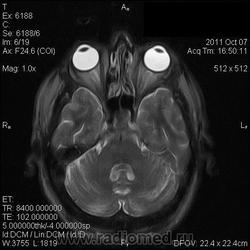

на МРТ - Определяется скопление крови в препонтинной цистерне, в проекции супраселлярной цистерны, в кортикальных бороздах полушарий головного мозга,  в проекции краниоспинального перехода. Выявляется горизонтальный уровень крови в задних рогах боковых желудочков. Боковые, третий желудочки резко расширены. Определяется перивентрикулярное повышение интенсивности сигнала от белого вещества головного мозга. Срединные структуры не смещены. Кортикальные борозды умеренно сглажены. Сильвиев водопровод прослеживается на всем протяжении. Отмечается смещение дна третьего желудочка каудально, с резким уменьшением размеров супраселлярной цистерны; базальные цистерны уменьшены в размере.

В проекции базальной артерии определяется аневризма размером до 4х6 мм.

Helios, Танюша а что конкретно у вас не укладывается между описанием и картинкой? Импульсные последовательности прикольные конечно; кровь выглядит не очень привычно, но это низкопольный Openmark. Какие еще варианы могут быть?

Мне напоминает FLAIR. В желудочках уровни крови и белое по субарахноидальным щелям тоже кровь. Аневризму тоже не вижу. Может долихоэктазия, если смотреть на сагитталы. Мелковато для меня, наверное.

Картинки действительно мелковаты. Я видел весь пакт изображений. Аневризма была хорошо видна на МР-ангиограммах, но Евгений их не выложил; а на обычных сканах ее четко не видно. Почему такие сигнальные характеристики у крови сложно сказать, я думаю, что в большую степень завязано давности кровоизлияния (четко не известно, когда оно произошло), на типе ИП и самом оборудовании... Такие вот мысли...